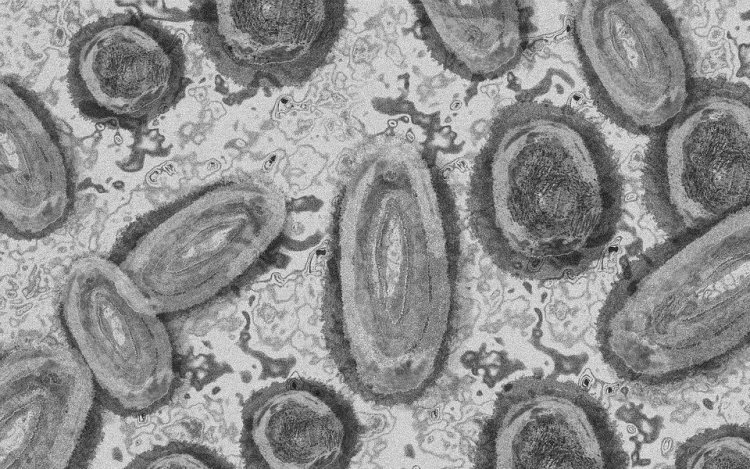

Meghaladta a 13 ezret a majomhimlő-fertőzöttek száma az Egyesült Államokban

Meghaladta a 13 ezret a majomhimlő-fertőzöttek száma az Egyesült Államokban, a legtöbb esetet Kaliforniában és New York államban regisztrálták.

Az amerikai járványügyi és betegségmegelőzési központ (CDC) szerdán közölt friss tanulmánya szerint a járvány ugyan elsősorban szexuális érintkezés útján terjed, de a fertőzöttek egy része tömegrendezvényeken kapta meg a vírust. A hivatal arra hívja fel a figyelmet, hogy a majomhimlővel bárki megfertőződhet, ha másokkal közeli testi kapcsolatba kerül, akár bőrfelületek érintkezése révén.

A legutóbbi adatok szerint 13 500 fölött van az igazolt fertőzöttek száma, az esetek csaknem felét Kalifornia, New York és Florida államokban regisztrálták.